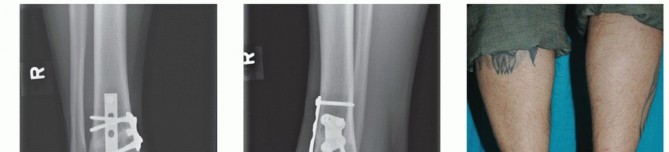

We routinely obtain simulated weight-bearing radiographs at 6 and 10 weeks and again at 14 to 16 weeks, depending on the progression of healing. If there was a concern about fixation of the graft or osteotomy, then radiographs are also obtained at the first postoperative visit (FIGS 1 , 2 and 3).

FIG 1 • Two-and-a-half-year follow-up. A. AP radiograph. B. Lateral radiograph. C. Clinical correlation.*

Gross et al2 reported on nine patients who underwent fresh osteochondral allograft transplantation. At a mean follow-up of 11 years, six grafts remained in situ. The three failed allografts demonstrated radiographic and intraoperative evidence of fragmentation or resorption, and these patients went on to ankle fusion. Standardized outcomes measures for comparison were not used in that study.

Raikin3 recently reported on 15 patients who underwent bulk fresh osteochondral allografting for large-

volume cystic lesions of the talus. The mean volume of the cystic lesions was 6059 mm3. At a mean followup of 4.5 years, the mean American Orthopaedic Foot and Ankle Society (AOFAS) ankle-hindfoot score was 83 points. Only two grafts failed and went on to have an ankle arthrodesis. Some form of graft collapse, graft resorption, or joint space narrowing was seen in all patients.

A retrospective review by Adams et al1 showed significant improvement in pain and the Lower Extremity Functional

Score (LEFS) at a mean follow-up of 48 months in eight patients who underwent osteochondral allograft transplantation of the talus. The mean postoperative AOFAS anklehindfoot score was 84 points. Three grafts were found to have graft-host lucencies in one plane on plain radiography. These patients were doing well and no further imaging was obtained. One patient continued to be symptomatic and was thought to have a nonunion of the graft due to circumferential lucency. Second-look arthroscopy demonstrated partial graft cartilage delamination but a stable graft. The patient did not wish to have any further treatment.

FIG 2 • Dorsiflexion. A. Radiograph (although the joint appears to narrow anteriorly, this phenomenon has not changed in 2 years and the patient experiences no pain or impingement). B. Clinical appearance.*

FIG 3 • Plantarflexion. A. Radiograph. B. Clinical correlation.*